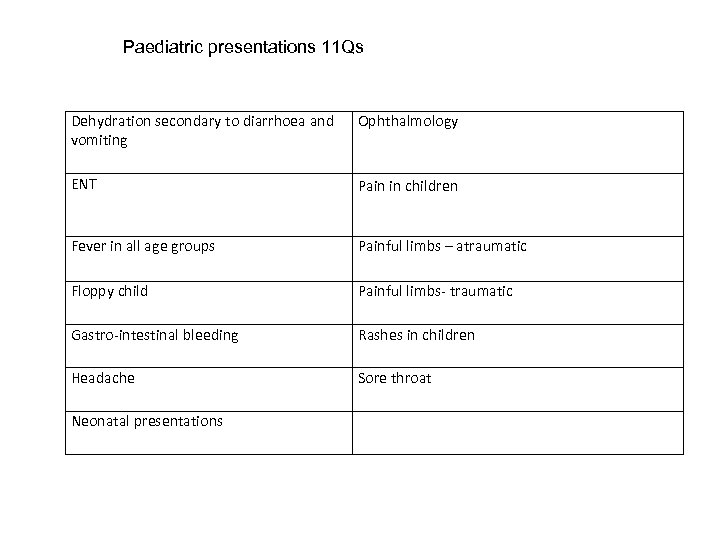

Paediatric presentations 11 Qs Dehydration secondary to diarrhoea and vomiting Ophthalmology ENT Pain in children Fever in all age groups Painful limbs – atraumatic Floppy child Painful limbs- traumatic Gastro-intestinal bleeding Rashes in children Headache Sore throat Neonatal presentations